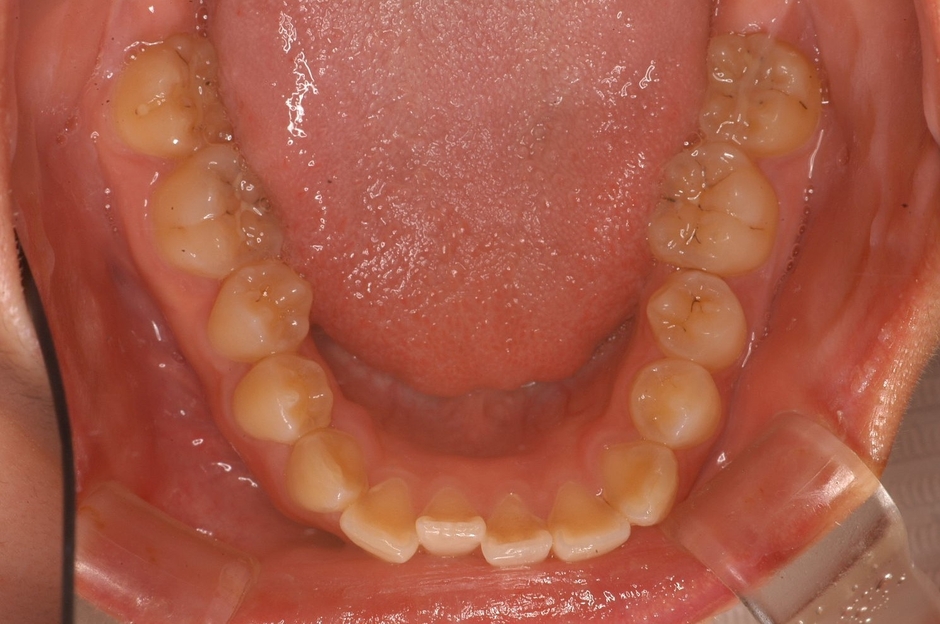

「理想的な歯並び」と「現代人に多い歯並び」の画像、これは何を意味しているのか?

歯並びの中にあるもの。それは、「舌」だったのです。

歯並びが小さいと「舌が窮屈」になり、アゴの位置がずれてしまいます。